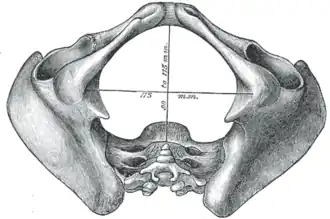

Diameters of inferior aperture of lesser pelvis (female)

Diameters of inferior aperture of lesser pelvis (female) -